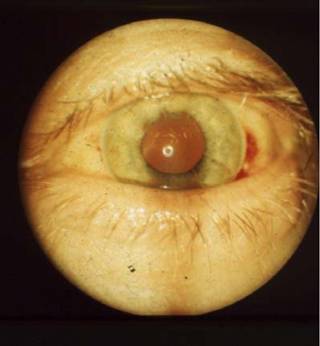

Рис. 2.2.9. Кератоконус IV степени

Рис. 2.2.10. Кератоконус IV степени, снимок сбоку